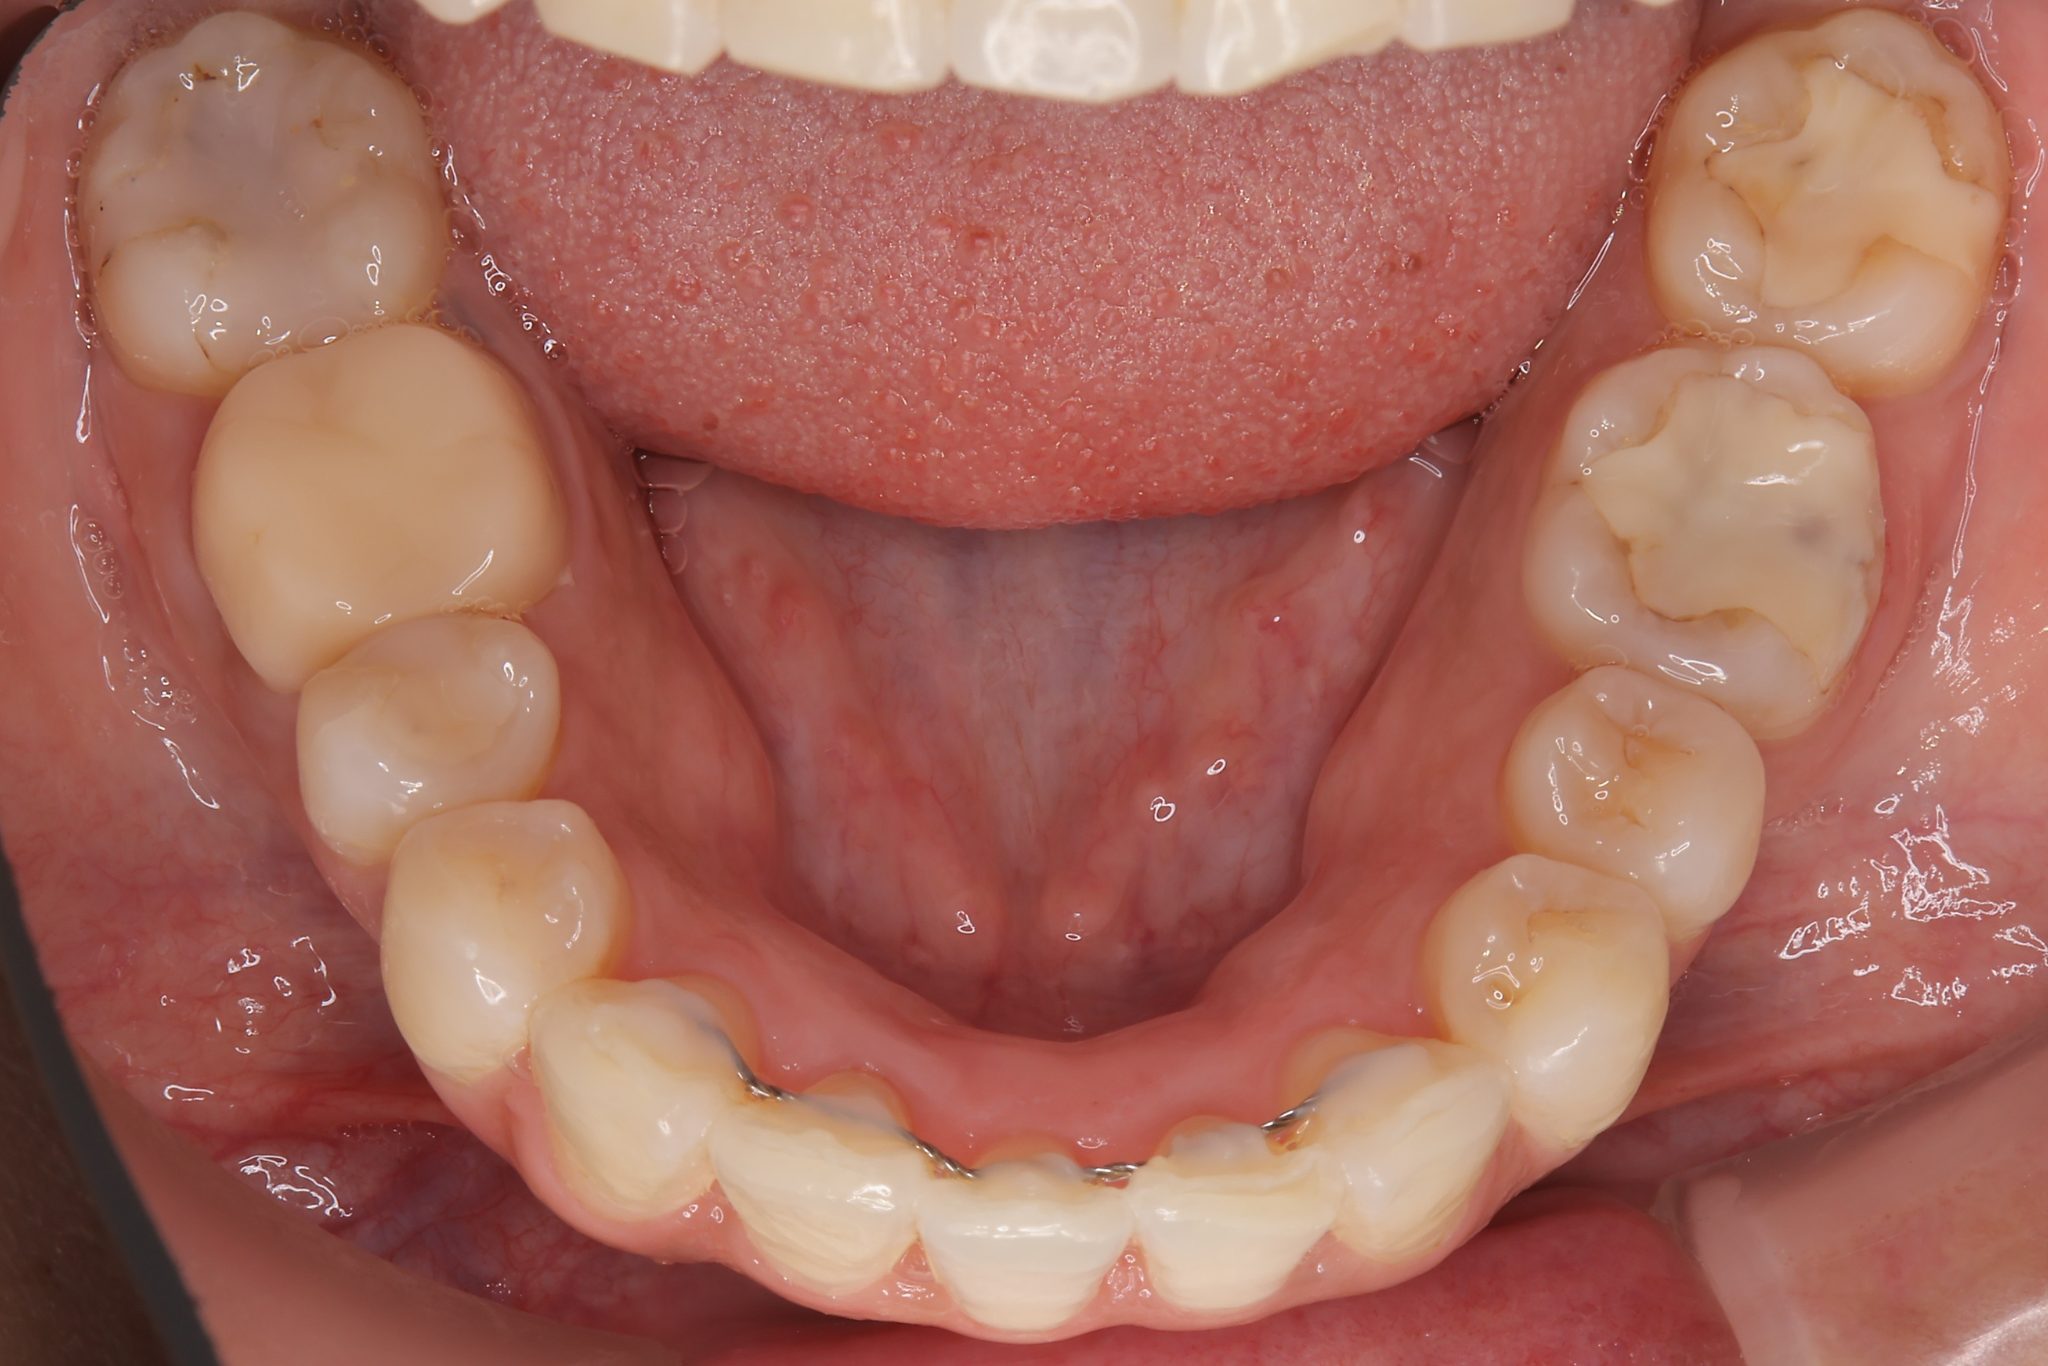

ビフォー

インビザライン矯正治療|症例_649